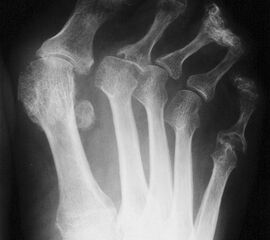

Konventionelle Röntgenaufnahmen sind das wichtigste bildgebende Verfahren. Die Aufnahmen zur OP-Planung sollten a.p. und streng seitlich im Stehen durchgeführt werden. Typische radiologische Veränderungen im Verlauf einer RA sind konzentrische Gelenkspaltverschmälerungen, gelenknahe Entkalkung, periartikuläre Weichteilschwellung, Erosionen der Gelenkflächen, später Zerstörung der Gelenkflächen mit Fehlstellungen sowie knöchernen Ankylosen oder Gelenkluxationen. Eine radiologische Stadieneinteilung erfolgt nach dem Schweregrad der destruierenden Veränderungen nach Larsen, Dale und Eek in 6 Stadien 3.

Dorsoplantare Darstellung des Vorfußes. Fortgeschrittene Destruktion des Metatarsophalangealgelenks am 5. Strahl und Lateraldeviation der Zehen.

Abbildung 4